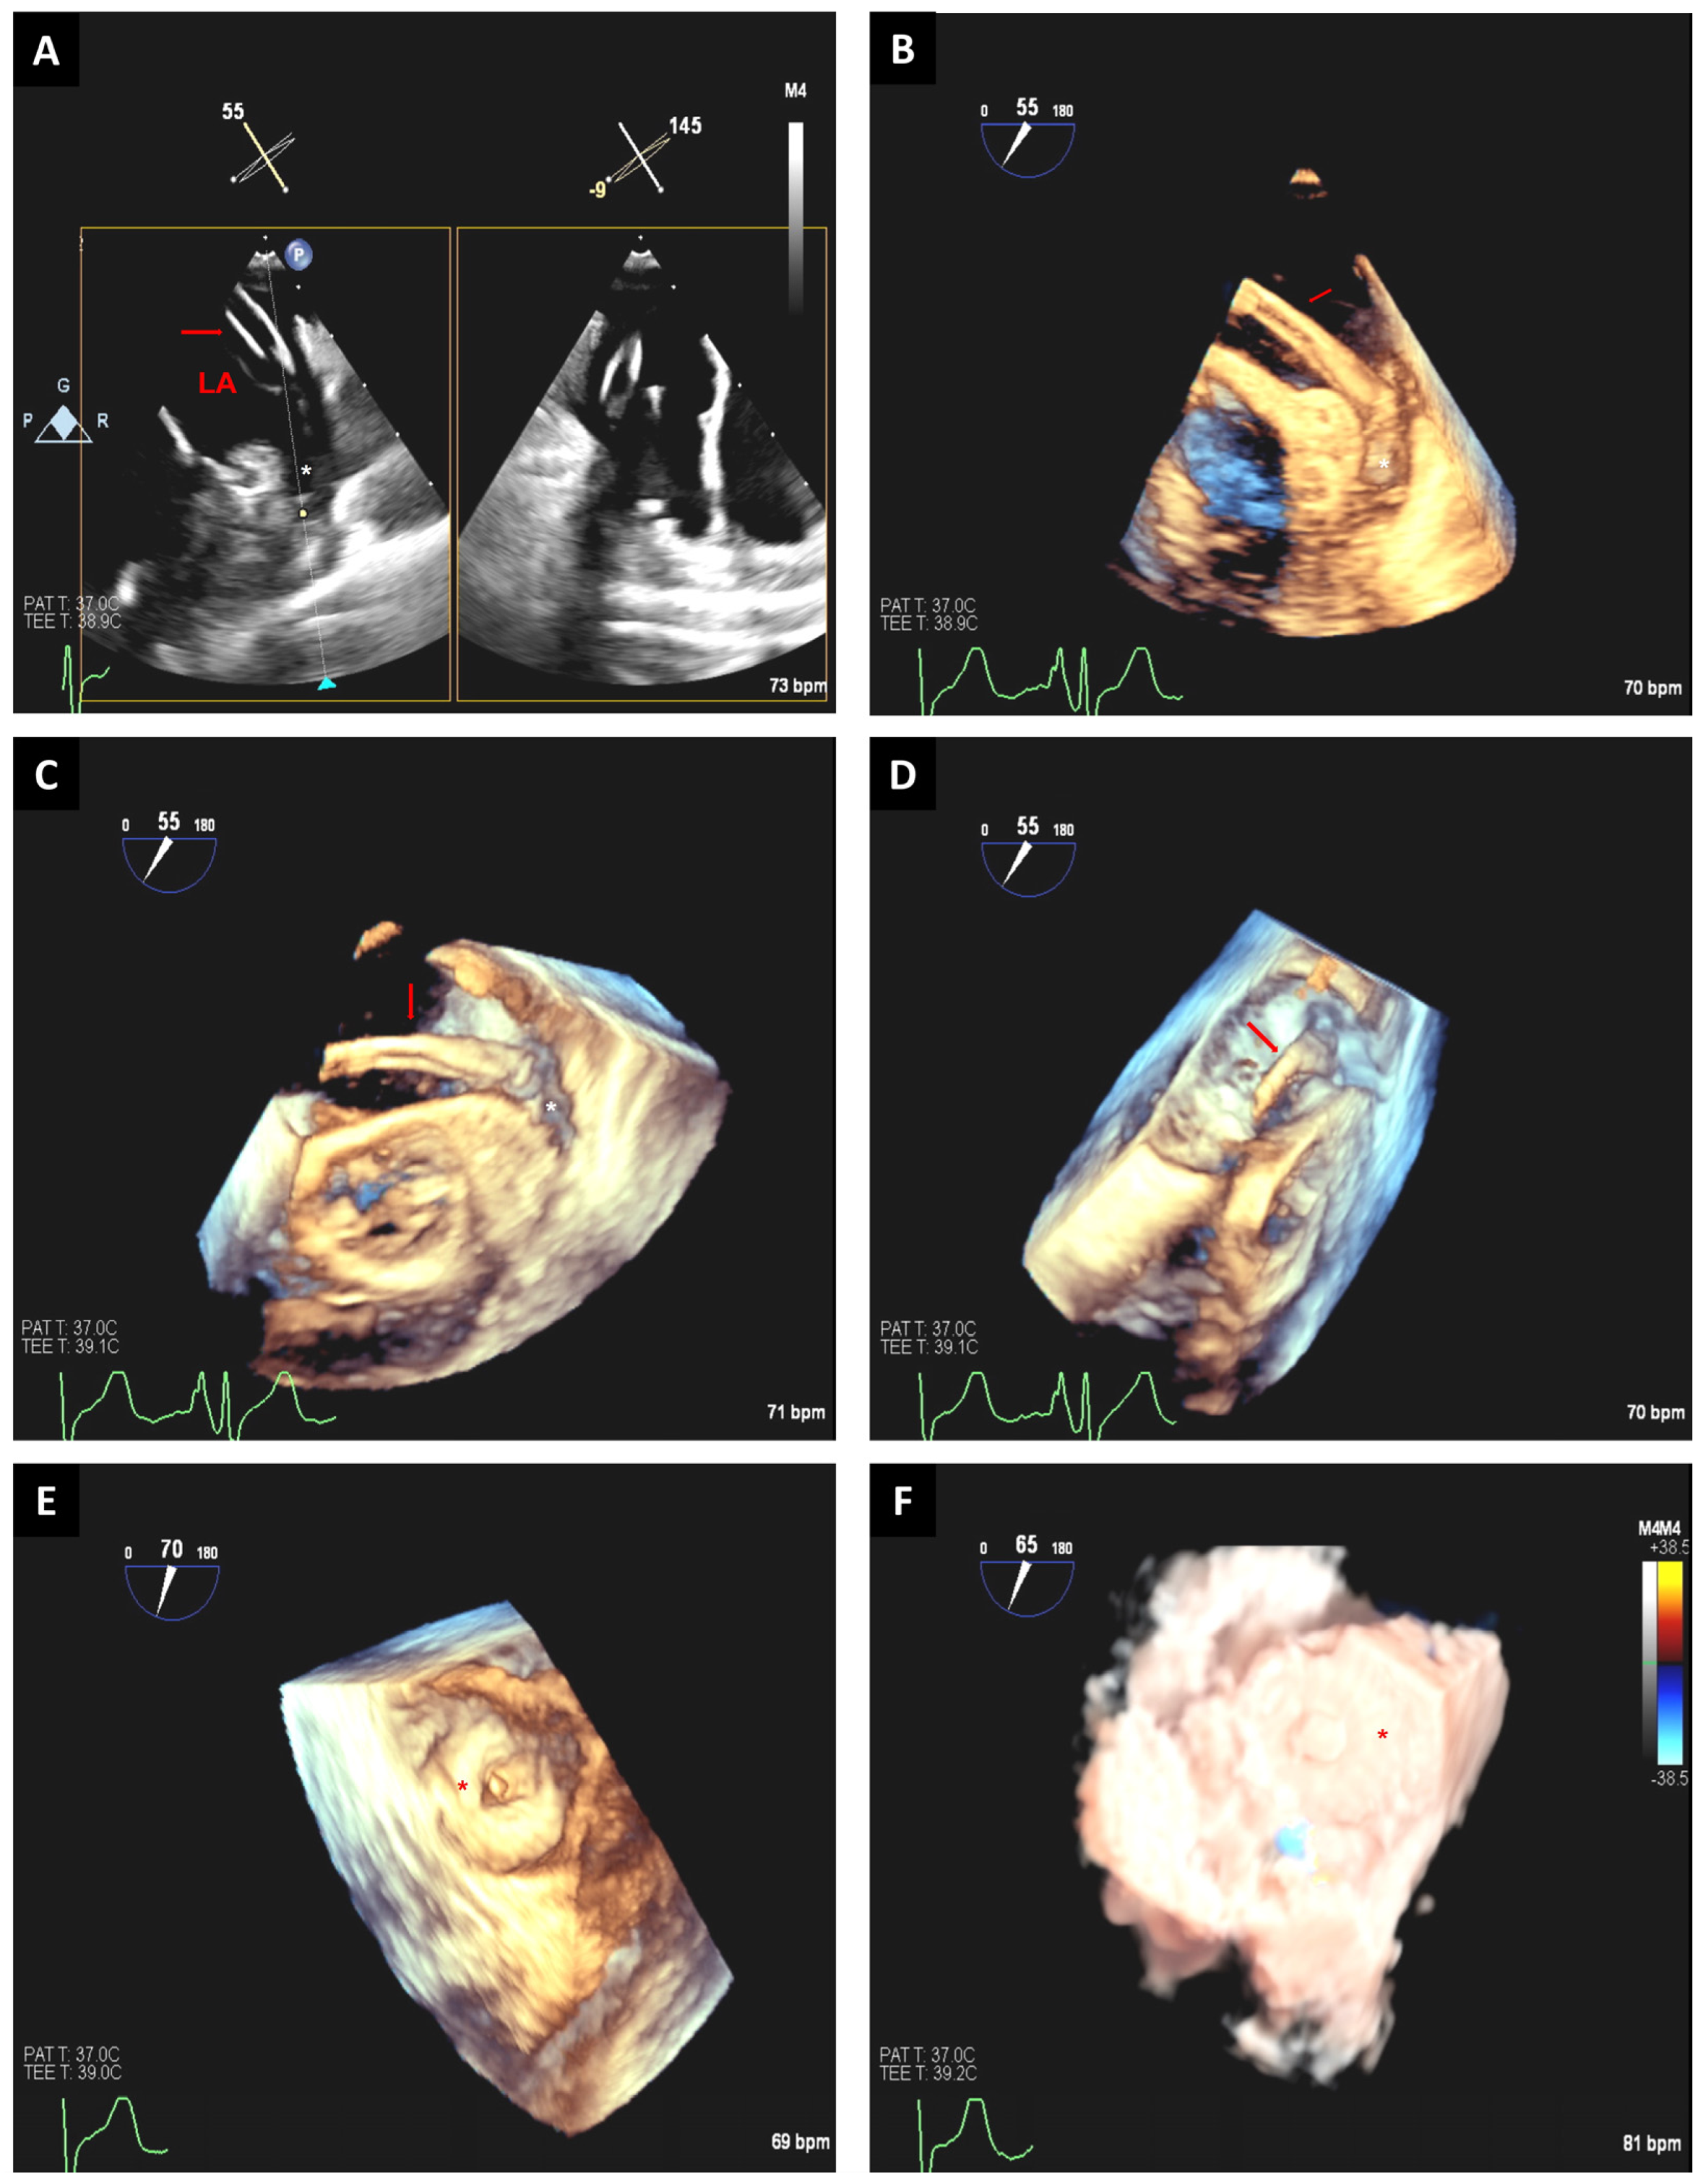

3.2.1. Edge-to-Edge Mitral Valve Repair

3.2.2. Transcatheter Mitral Valve Replacement

3.3. Paravalvular Leak Closure

3.4. Tricuspid Valve Interventions